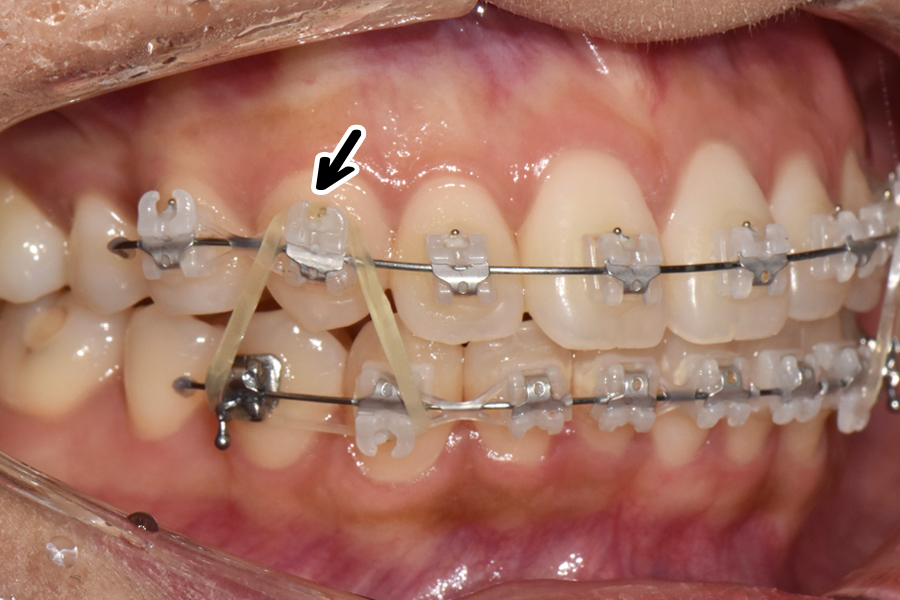

초창기에 교정장치를 부착하고 1차 배열을 한 뒤, 대략 2개월이 지난 후의 모습입니다. 생각보다 환자분의 치아가 잘 움직여주셔서 처음보다 치아 배열이 많이 펴져 있는 것을 볼 수 있습니다.

일반적인 미니튜브 교정 같은 경우에는 치아를 2차원적으로 밖에 움직일 수 없는데 클리피씨 교정 같은 경우에는 조금 더 치아를 정밀하게 움직이고 3차원적으로 치아를 조절할 수 있는 면이 있기 때문에 고무줄로 더 정밀한 교합을 만들고 있는 것을 보실 수 있습니다.

옆에서 보면 표시된 부분이 좀 많이 떠있기 때문에 고무줄을 이용해 붙잡고 있는 것을 보실 수 있고, 아래에서는 작은 고무줄을 이용해 치아를 회전시키는 것을 볼 수 있습니다.